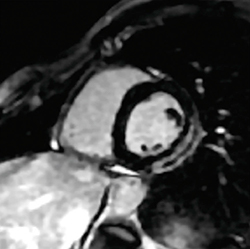

3.Single Shot Myocardial Delayed Enhancement

“Single Shot Myocardial Delayed Enhancement(以下,SS MDE)”は,FIESTAまたはfast GREシーケンスにIR Pulseを追加したsingle shotでの遅延造影のアプリケーションである。従来,遅延造影を撮像する場合には,1スライスあたり15秒程度の息止めを必要としていた。このため,左室心筋全域の短軸像を撮像しようとすると,その範囲を覆うためには10スライス程度必要となり,患者は多くの呼吸停止を繰り返すことになる。これは,特に高齢者や小児の患者の遅延造影撮像の際に,大変な労力を強いられることとなる。

SS MDEは,1心拍あたりに1スライスずつ撮像できるようになっている。これにより,1回の呼吸停止時間を短縮,または呼吸停止なしでの撮像を可能とし,今まで撮像が困難だった患者の遅延造影を撮像することができるようになる。また,single shotの撮像法のため,動きの影響が少ない心筋遅延造影撮像が可能となった。

さらに,本来の縦磁化のコントラストを反映させたphase sensitive imageの併用が可能で,TI値の相違に依存しない遅延造影画像を取得することで,心筋がnullに達せず再撮像するリスクを減らすことができる(図3)。

図3 SS MDE